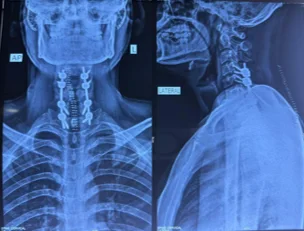

Before & After Clinical Gallery

We showcase real patient cases (with consent), including:

• Pre- and Post-operative MRIs and X-rays

• Disc Herniations, Stenosis, and Spondylolisthesis cases

• Visible improvement in alignment and decompression

Before

After